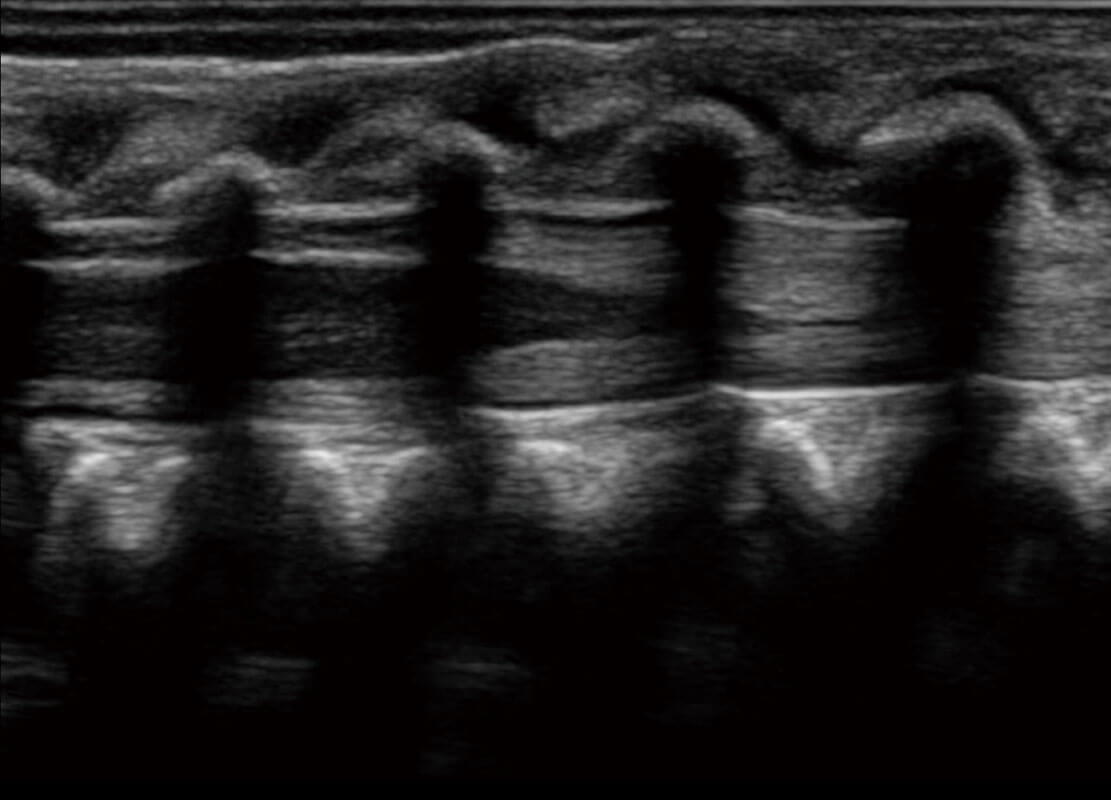

腔内妇科-宫腔分离

腔内妇科-卵巢

腔内三维-宫内节育器

腔内三维-光影成像